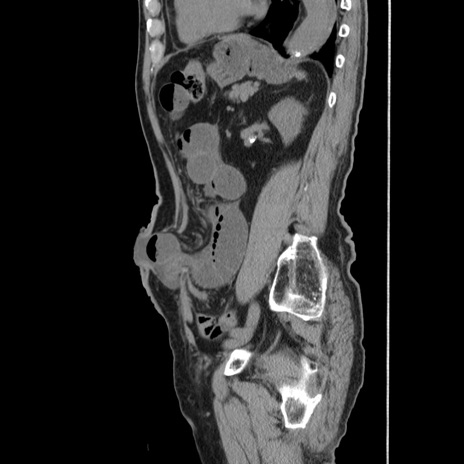

症例24(矢状断像)

【症例】80歳代男性

【主訴】左側腹部痛、嘔吐

【現病歴】本日早朝より左腹部に痛みあり。昼頃嘔吐認めたため、救急要請。

【既往歴】直腸癌(Mile手術)、胆摘

【身体所見】意識清明、BT 35.9℃、BP 221/93mmHg、SpO2 97%(RA) 、腹部:左ストーマ周囲に限局性の腹部膨隆あり。 膨隆部自発痛・圧痛あり・軟。

【データ】WBC 7700、CRP 0.09